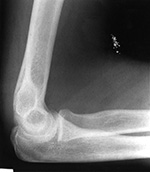

Deliberate injection of mercury subcutaneously or intravenously produces a dramatic radiographic appearance (figure: mercury in left elbow; figure: mercury in the lungs). Individuals may inject themselves in the mistaken belief that mercury increases their strength, or they may be drug abusers or even attempting suicide (Naidich, 1973; Wenzel, 1980; Peterson, 1980; Spizarny, 1987).

If mercury is injected into subcutaneous tissues, it forms irregular globules and may remain in place for months to years. If it is injected into the venous system, it will embolize to the lungs where it forms small globules in the peripheral branches of the pulmonary arteries. The mercury may also pool in the right ventricle. Differentiating aspirated metallic mercury from mercury embolism to the lungs is difficult on the basis of chest radiographic appearances alone. The diagnosis depends on the patient history, presence of mercury in the right ventricle or subcutaneous tissue of the arm or leg (favoring mercury embolism) or the presence of mercury in the gastrointestinal tract (favoring mercury aspiration) (Wenzel, 1980; Peterson, 1980; Spizarny, 1987). Surprisingly, metallic mercury in the bronchial tree or in the pulmonary arterial tree is usually not associated with symptoms, and it may remain undiscovered indefinitely.

21 year-old man who injected himself with metallic mercury.

Metallic mercury in the lungs Metallic mercury in the left elbow Halloween candy MR artifacts from tiny metallic deposits

Mercury in the chest Mercury in the elbow Candy Shoulder MRI metallic artifacts

21 year-old man who injected himself with metallic mercury. There are mercury emboli to the lungs and metallic mercury is evident in the antecubital fossa of the left elbow. (Figures courtesy of Charles A. Rohrmann, Jr, MD. They were originally printed in Peterson, 1980). Trick or treat candy. There are no hidden needles or razor blades. The candy and the apple (round density) where eaten with much enjoyment. From Hunter, 1994